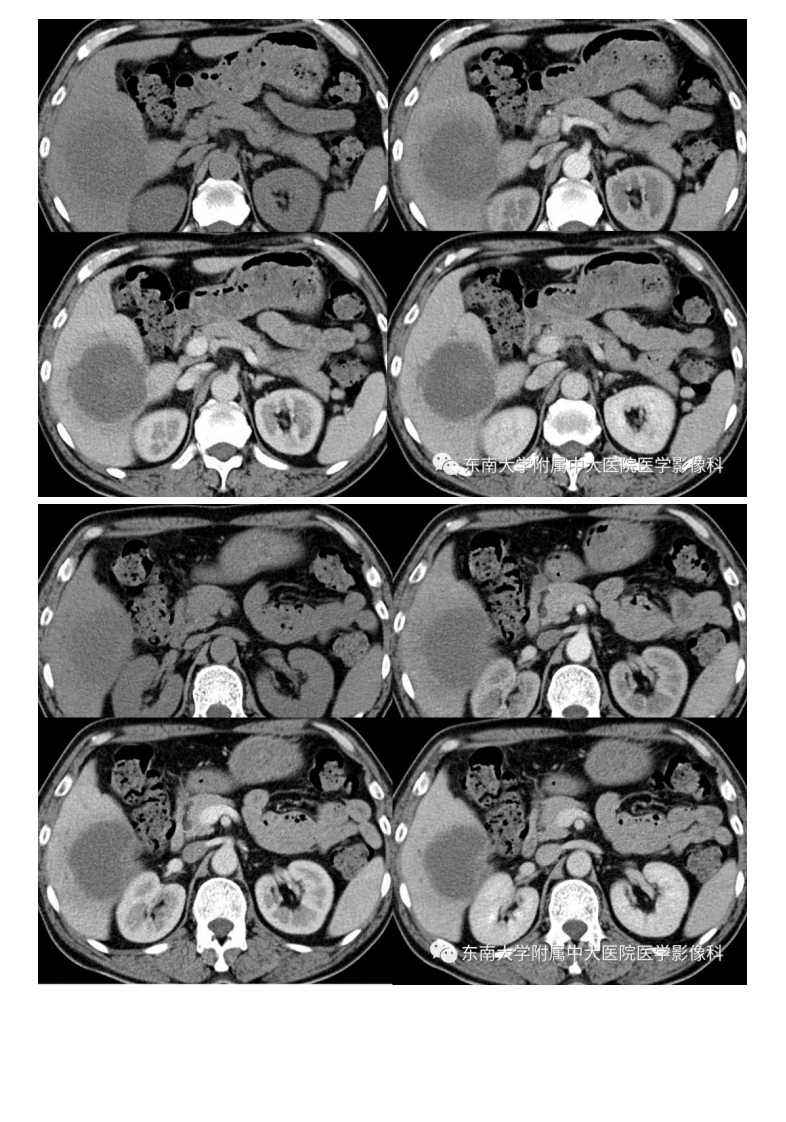

20191230_2【晨读结果公布】2019.12.30消化系统疾病.pdf